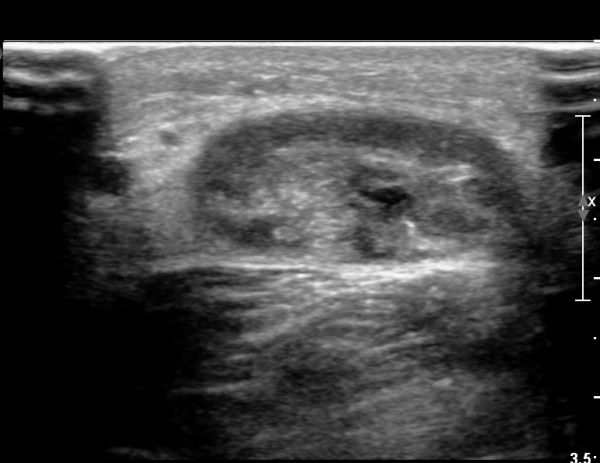

¾ÆÅ³·¹½º°Ç Á¾´Ü¸é°Ë»ç¿¡¼­ ¾ÆÅ³·¹½º°Ç ¸»´ÜºÎ¿¡ ¾ÆÅ³·¹½º°ÇÀÇ Àú¿¡ÄÚºÎÁ¾, ±¹¼ÒÀû ¿¬°á¼º ¼Ò½Ç,

¹ß¸ñ°üÀý ÈĹæºÎ¿¡ ¼ö¾×Àú·ù°¡ °üÂûµÊ(»çÁø 3, 4, 5).